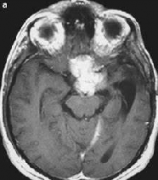

脑膜瘤严重吗?不足9%的颅内脑膜瘤位于后颅窝。Olivercrona等报道了4185例脑肿瘤,颅内脑膜瘤为803例,有68例位于后颅窝(包括20例小脑幕脑膜瘤)。由于后颜窝的...